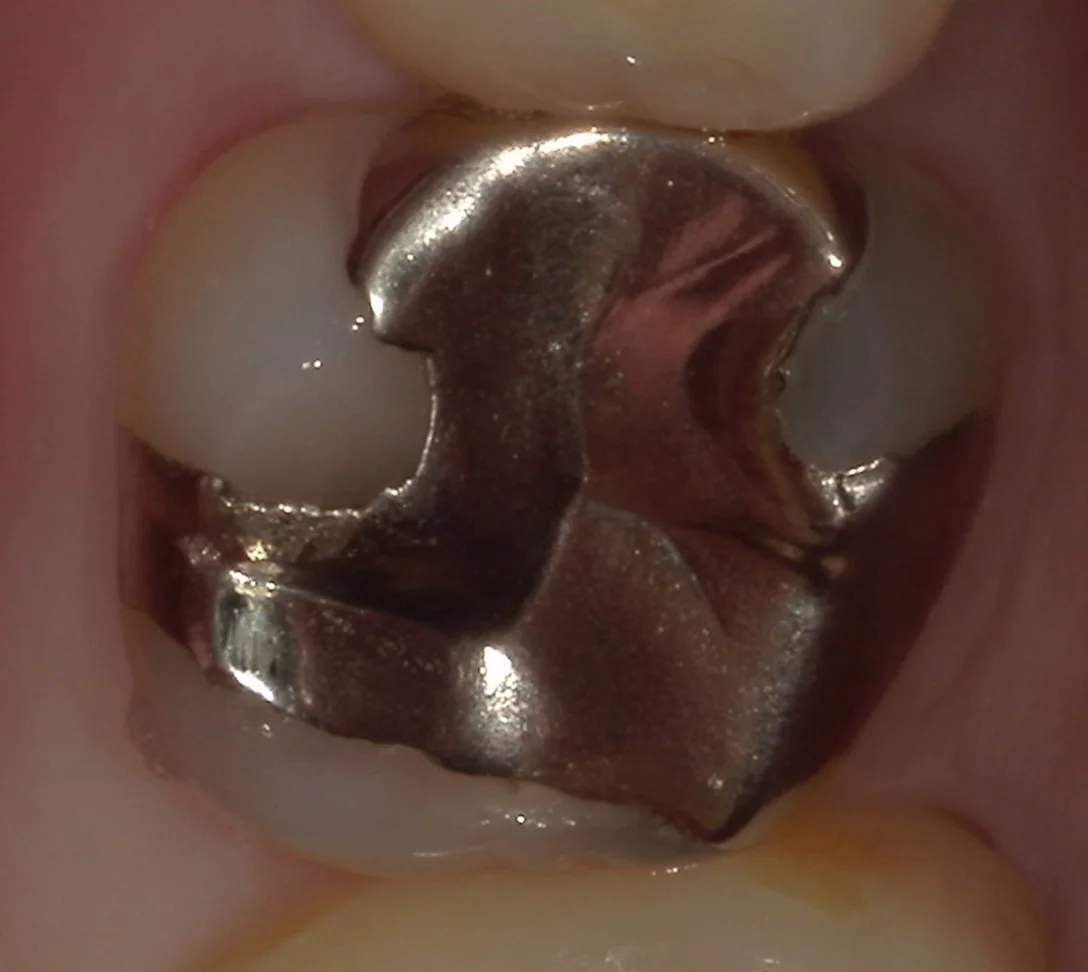

まずは術前の噛む面からの写真です。

非常に広範囲に金属の詰め物が詰められているのが分かるかと思います。

また、歯茎の際辺りが歯ブラシの圧で抉れてしまっています。

こういった状態を「楔状欠損」と言い、実はダイレクトボンディングの中で治療が最も難しいと言われている状態になります。